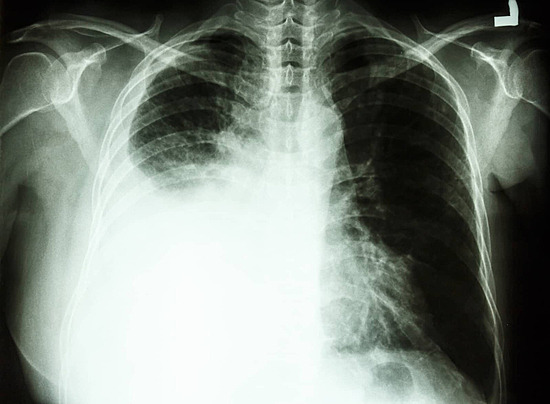

胸のレントゲンで、水のラインが下がっていると医師から言われました。呼吸が深くできるようになり、少しずつ食事が美味しいと感じられるようになりました。

結局、この2ヶ月間は一度も水を抜かずに過ごせています。レントゲンでは悪化は見られず、顔色が明るくなり、散歩ができるまで体力が回復しました。